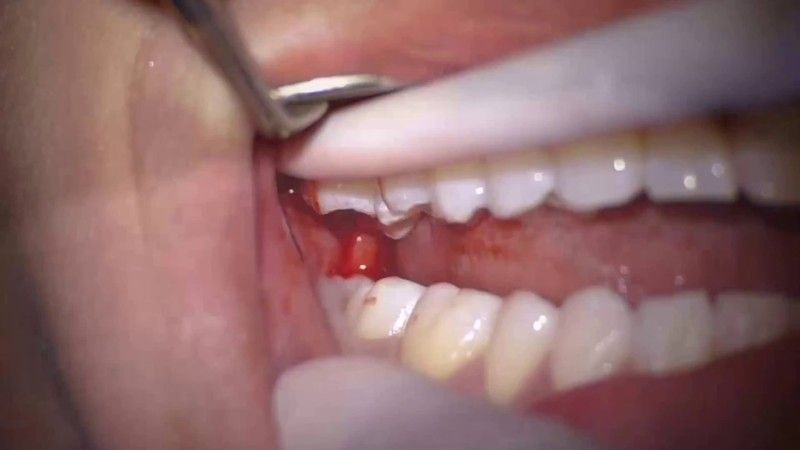

Trước đây, khi nhắc đến nhổ răng khôn mọi người thường nghĩ đến kiềm bẫy, kim tiêm…. Tuy nhiên, nhờ sự phát triển của công nghệ hiện đại, tình trạng đau nhức khi nhổ răng khôn đã được giảm thiểu đến mức thấp nhất. Với công nghệ nhổ răng khôn hiện đại bằng sóng siêu âm Piezotome, quá trình nhổ răng được diễn ra nhanh chóng, chỉ 15-30 phút. Vết thương sau khi nhổ sẽ nhanh chóng hồi phục, hạn chế tối đa tình trạng đau nhức, sưng tấy cho bệnh nhân.

Tuy nhổ bỏ răng khôn ngày nay chỉ là một tiểu phẫu đơn giản, nhanh chóng với sự hỗ trợ của máy móc hiện đại nhưng vẫn phải được thực hiện theo một quy trình nhất định. Điều này giúp bác sĩ giám sát từng bước của toàn bộ quy trình. Đồng thời, bệnh nhân cũng có thể dễ dàng theo dõi tình hình răng miệng của mình, qua đó đảm bảo tối đa mức độ an toàn.